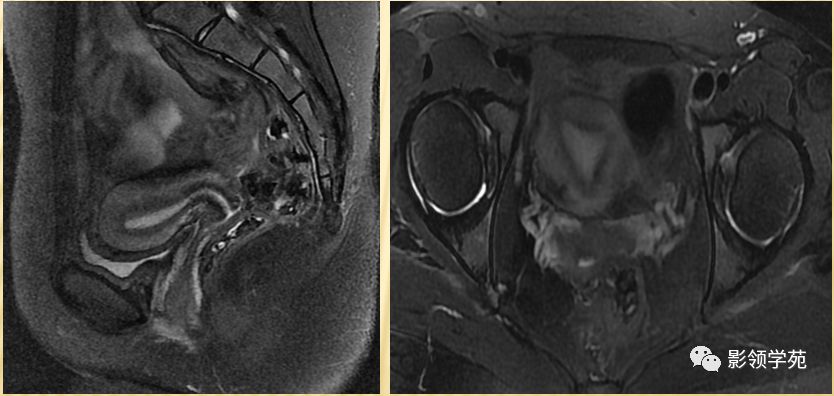

宫颈四层:

高信号---宫颈管黏液

稍高信号---宫颈黏膜皱襞;

低信号---宫颈纤维基质(与宫体JZ连续)

等信号---宫颈肌层

宫颈

T1WI表现为较均匀一致的稍低信号

高分辨率T2WI可看到4层结构

最内层-高信号粘液

粘膜层(柱状上皮)-高信号,低于粘液信号

纤维间质(结合带)-低信号

肌层-中等信号

阴道壁

阴道粘膜 为复层鳞 状上皮

T1WI 呈中等稍低信号

T2WI内带:高信号(上皮、粘液)

外带 :低信号

正常MR表现:卵巢和输卵管

卵巢:轴位和冠状面显示较佳,T1WI为中等或稍低信号,T2WI可因多个卵泡结构表现为高信号,但其间质部分仍呈稍低信号